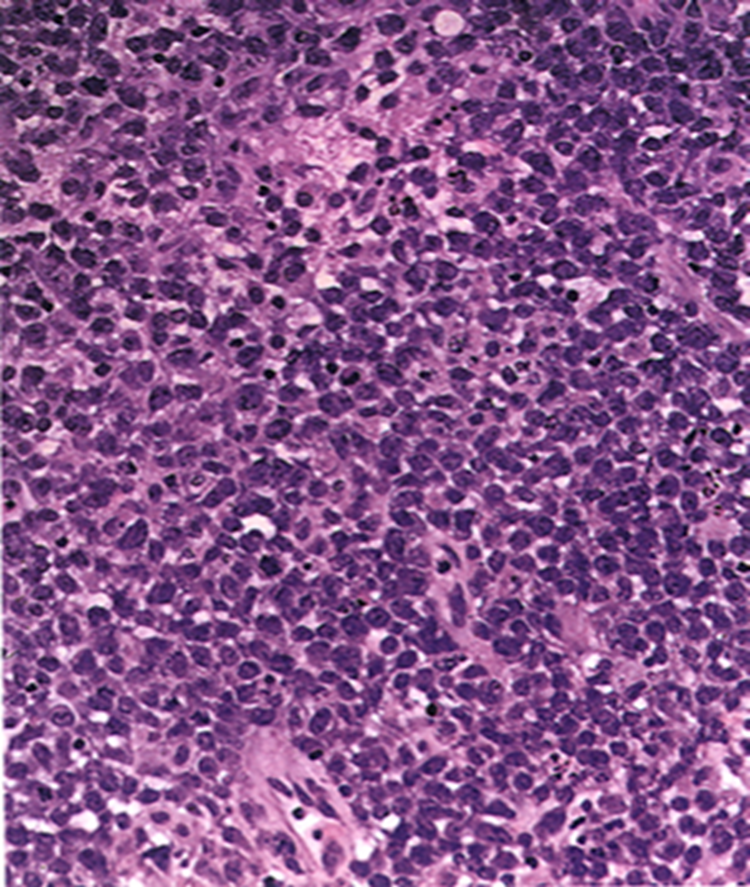

Sea of blue cells lymphocytes

Primary CNS lymphoma